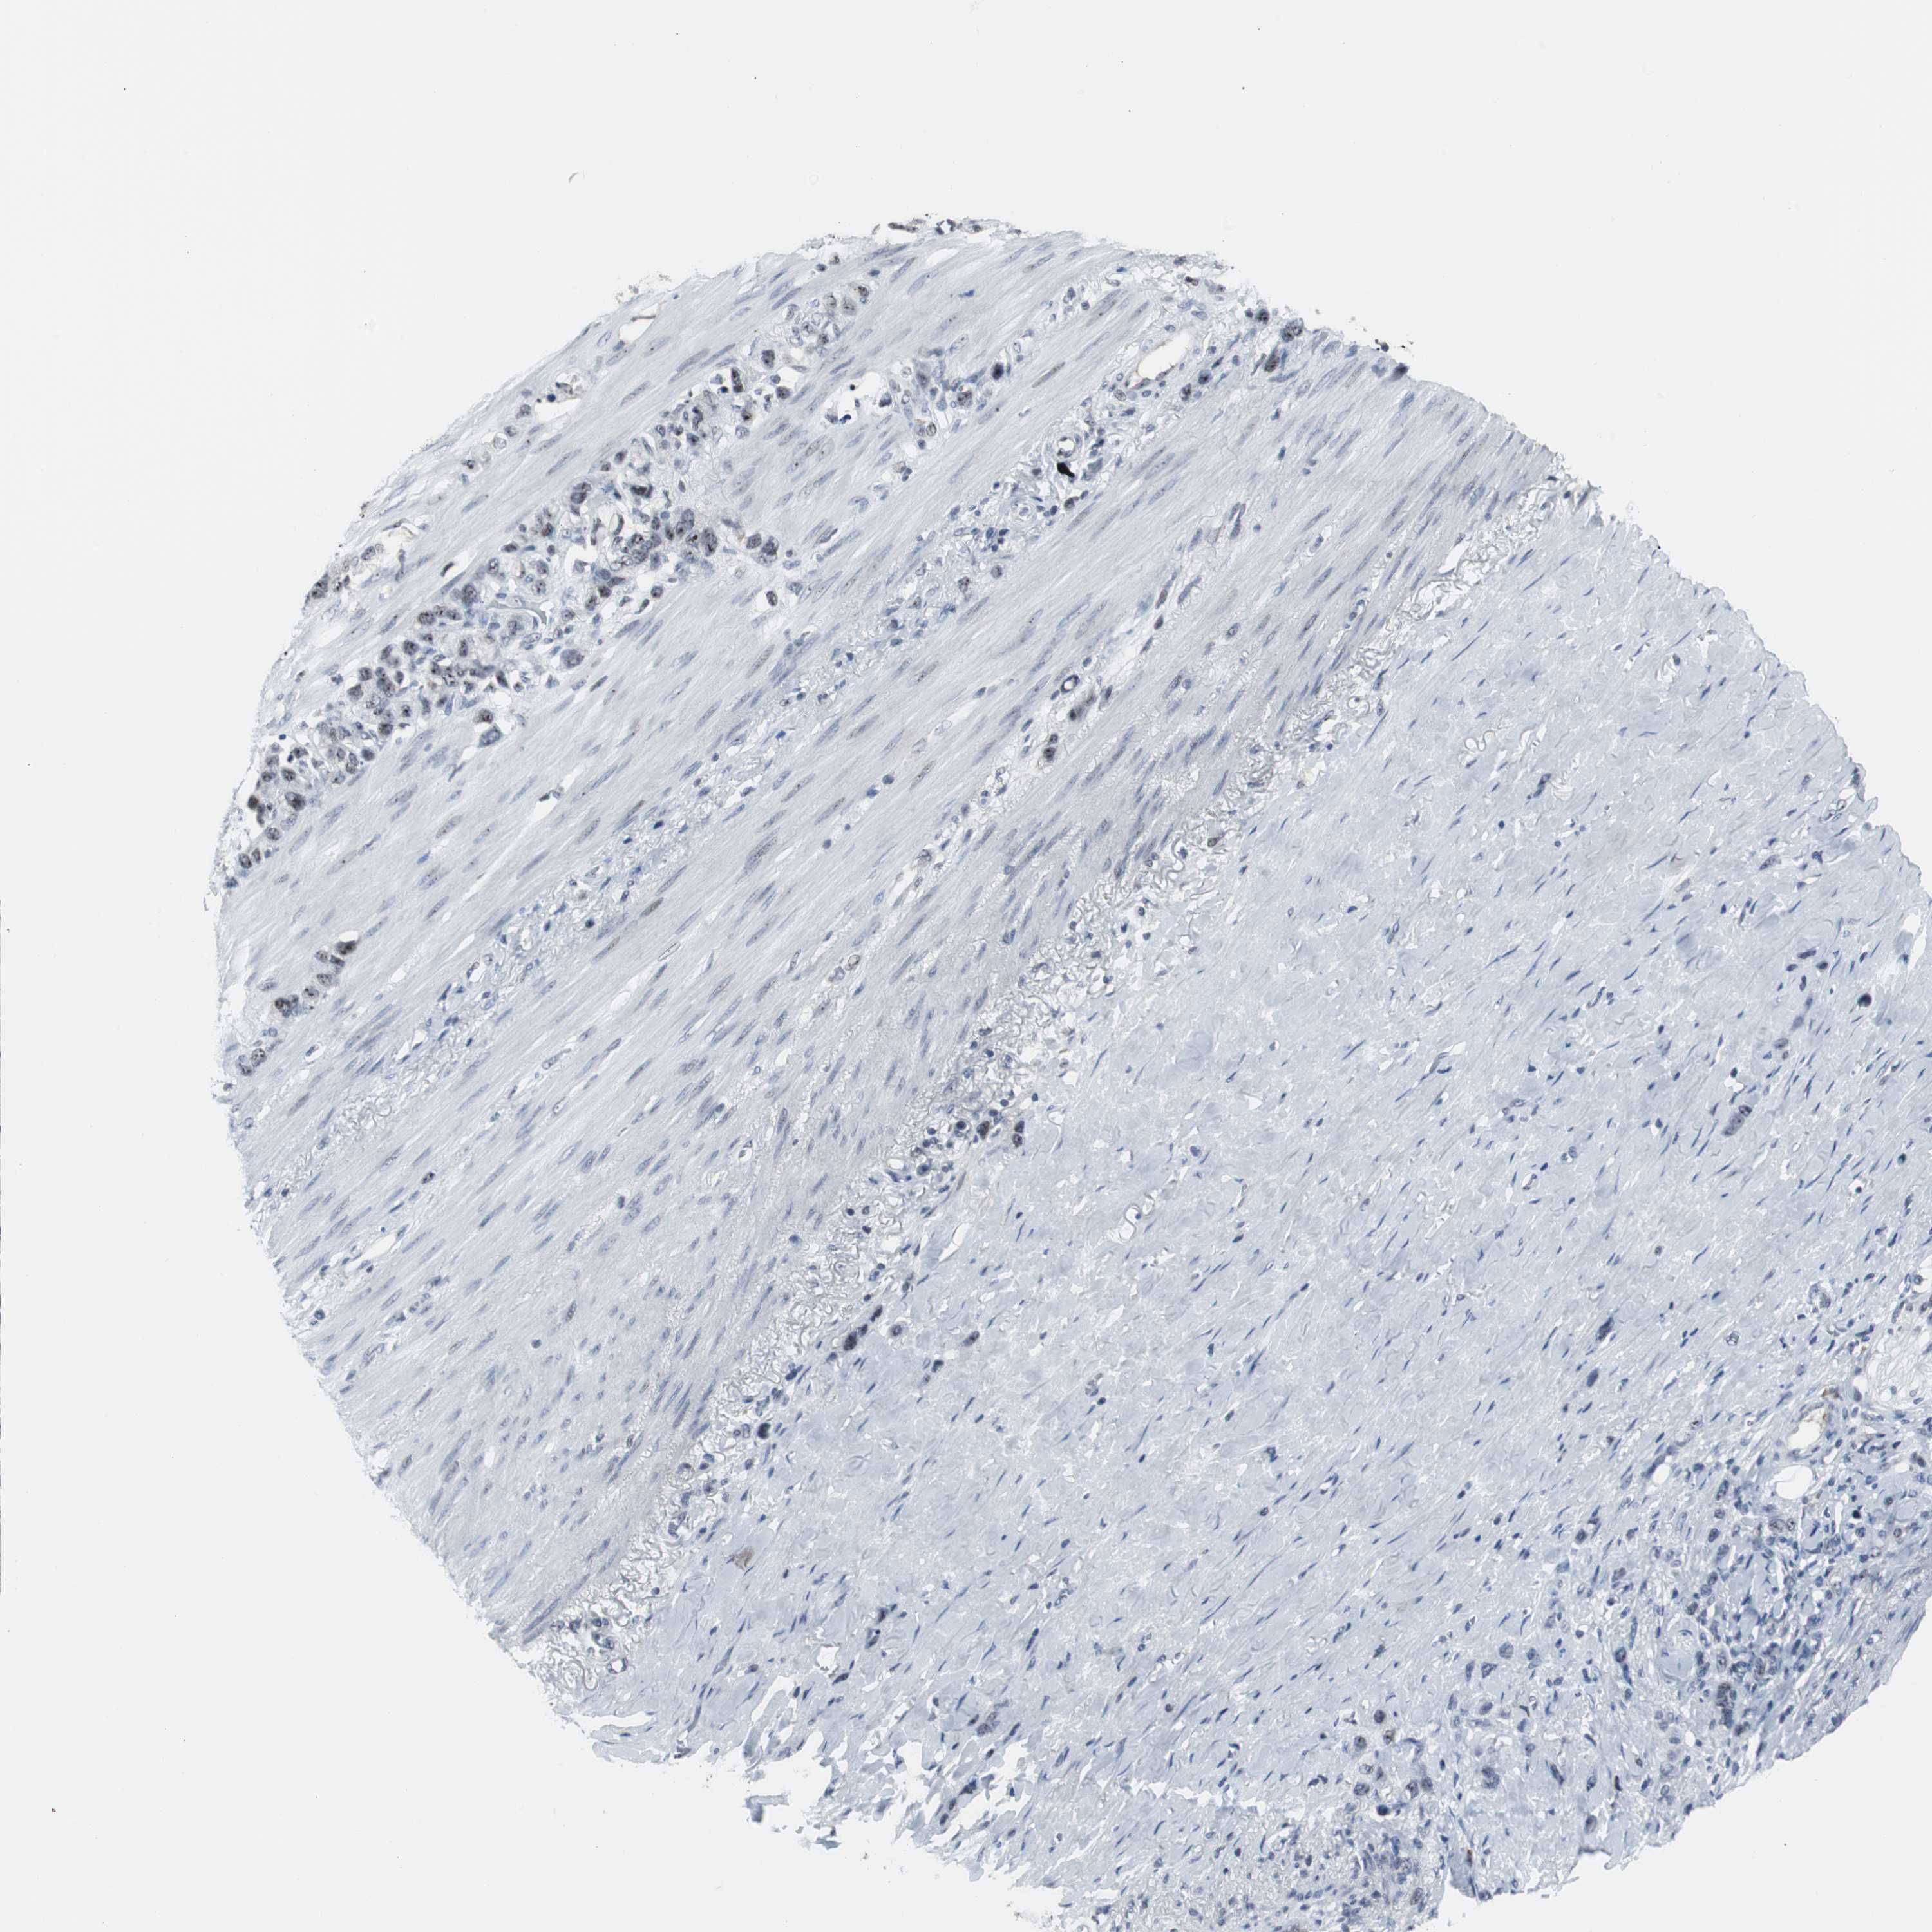

STOMACH CANCER - Protein expressioni

A mouse-over function shows sample information and annotation data. Click on an image to view it in a full screen mode. Samples can be filtered based on level of antibody staining by selecting one or several of the following categories: high, medium, low and not detected. The assay and annotation is described here.

Antibody stainingi

Antibody staining in the annotated cell types in the current human tissue is reported as not detected, low, medium, or high, based on conventional immunohistochemistry profiling in selected tissues. This score is based on the combination of the staining intensity and fraction of stained cells.

Each image is clickable and will lead to virtual microscopy that enables deeper exploration of all samples and also displays staining intensity scores, fraction scores and subcellular localization as well as patient and tissue information for each sample.

Antibody CAB004224

Staining

High

Medium

Low

Not detected

Intensity

Strong

Moderate

Weak

Negative

Quantity

>75%

75%-25%

<25%

None

Location

Nuclear

Cytoplasmic/membranous

Cytoplasmic/membranous,nuclear

Adenocarcinoma, NOS

Adenocarcinoma, High grade